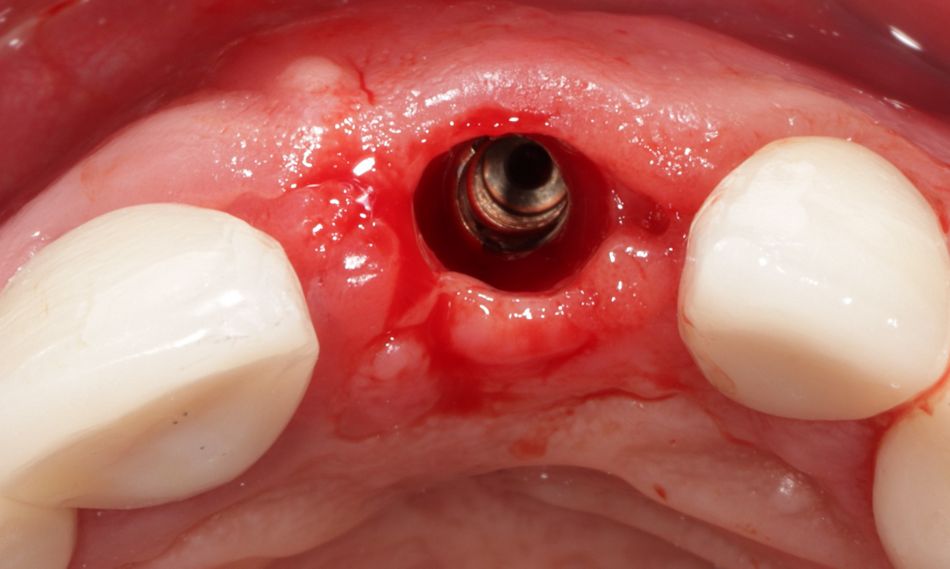

Nach einer präoperativen Planung wurde der frakturierte Zahn 11 behutsam unter maximaler Schonung der Alveolenwände extrahiert (Abb. 6). Die Alveole blieb intakt; Hart- sowie Weichgewebe waren unversehrt. Ein Vorteil der Sofortimplantation ist der direkte Zugang zur Alveole. Es kann lappenfrei gearbeitet werden, die Blutversorgung bleibt erhalten, Narbengewebe (z. B. durch vertikale Entlastungsschnitte) wird vermieden [12, 5]. Das Trauma und die Unterbrechung der Blutversorgung des Knochens durch das Bilden eines Mukoperiostlappens kann eine Resorption des Knochenvolumens begünstigen [13]. Das lappenfreie Vorgehen ist wenig invasiv und bringt in der Regel eine geringe postoperative Belastung für den Patienten mit. Allerdings bedarf es auch implantologischer Erfahrung, da beispielsweise die Sichtverhältnisse eingeschränkt sind.

Verwendet wurde im vorliegenden Fall das Implantatsystem Procone (Medentika). Die Aufbereitung des Implantatbettes regio 11 erfolgte nach Bohrprotokoll bis zum Durchmesser 4,3 mm. Der Spalt zum fazialen Knochen wurde mit einem bovinen Augmentat (Cerabone, Straumann) gefüllt. Zur verbesserten Wundheilung sind sowohl das Implantat als auch das Cerabone vor dem Einsetzen mit patienteneigenem Blutplasma bzw. Wachstumsfaktoren (iPRF) benetzt worden (Abb. 7 und 8). Das Implantat wurde nach dem Gewindeschneiden palatinal orientiert inseriert, sodass der Einbringpfosten bukkal hinter der fazialen Fläche der Nachbarzähne platziert war. Der Verschluss erfolgte erstmal mit einer Einheilkappe (Höhe 2 mm) (Abb. 9).